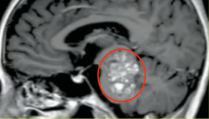

这个盘踞在脑干核心区(中脑-脑桥)的巨大海绵状血管瘤,影像呈现如同被虫蛀空的树干般布满骇人的病变斑点,每一次出血都可能造成可怕的神经损伤。

INC巴特朗菲教授曾做关于脑干海绵状血管瘤的专题报告,其中介绍了这则巨大脑干海绵状血管瘤的全切案例,本来已经偏瘫、面瘫的25岁女性经历了一场安全且全切的手术切除,从此之后站了起来。

25岁青年女性,偏瘫、面瘫,共济失调

(中脑-脑桥)脑干巨大海绵状血管瘤。术前影像:中脑、脑桥巨大占位